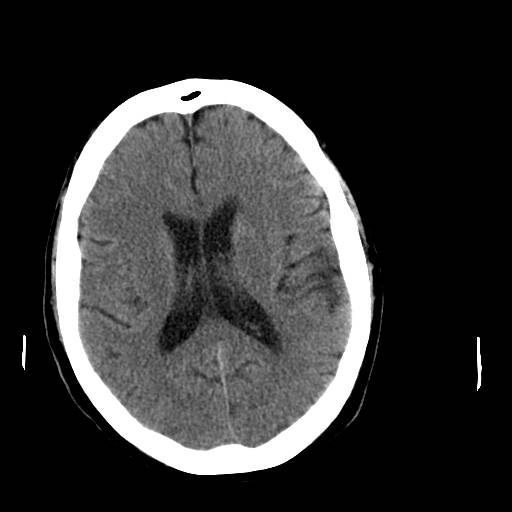

Hjernen, normal, CT

CT-skanning af normal hjerne uden kontrast hos en yngre person.